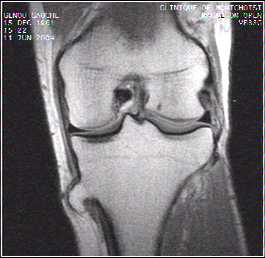

Musculosketal cases

Head and neck cases

Spine cases

Abdominal cases

Soft parts